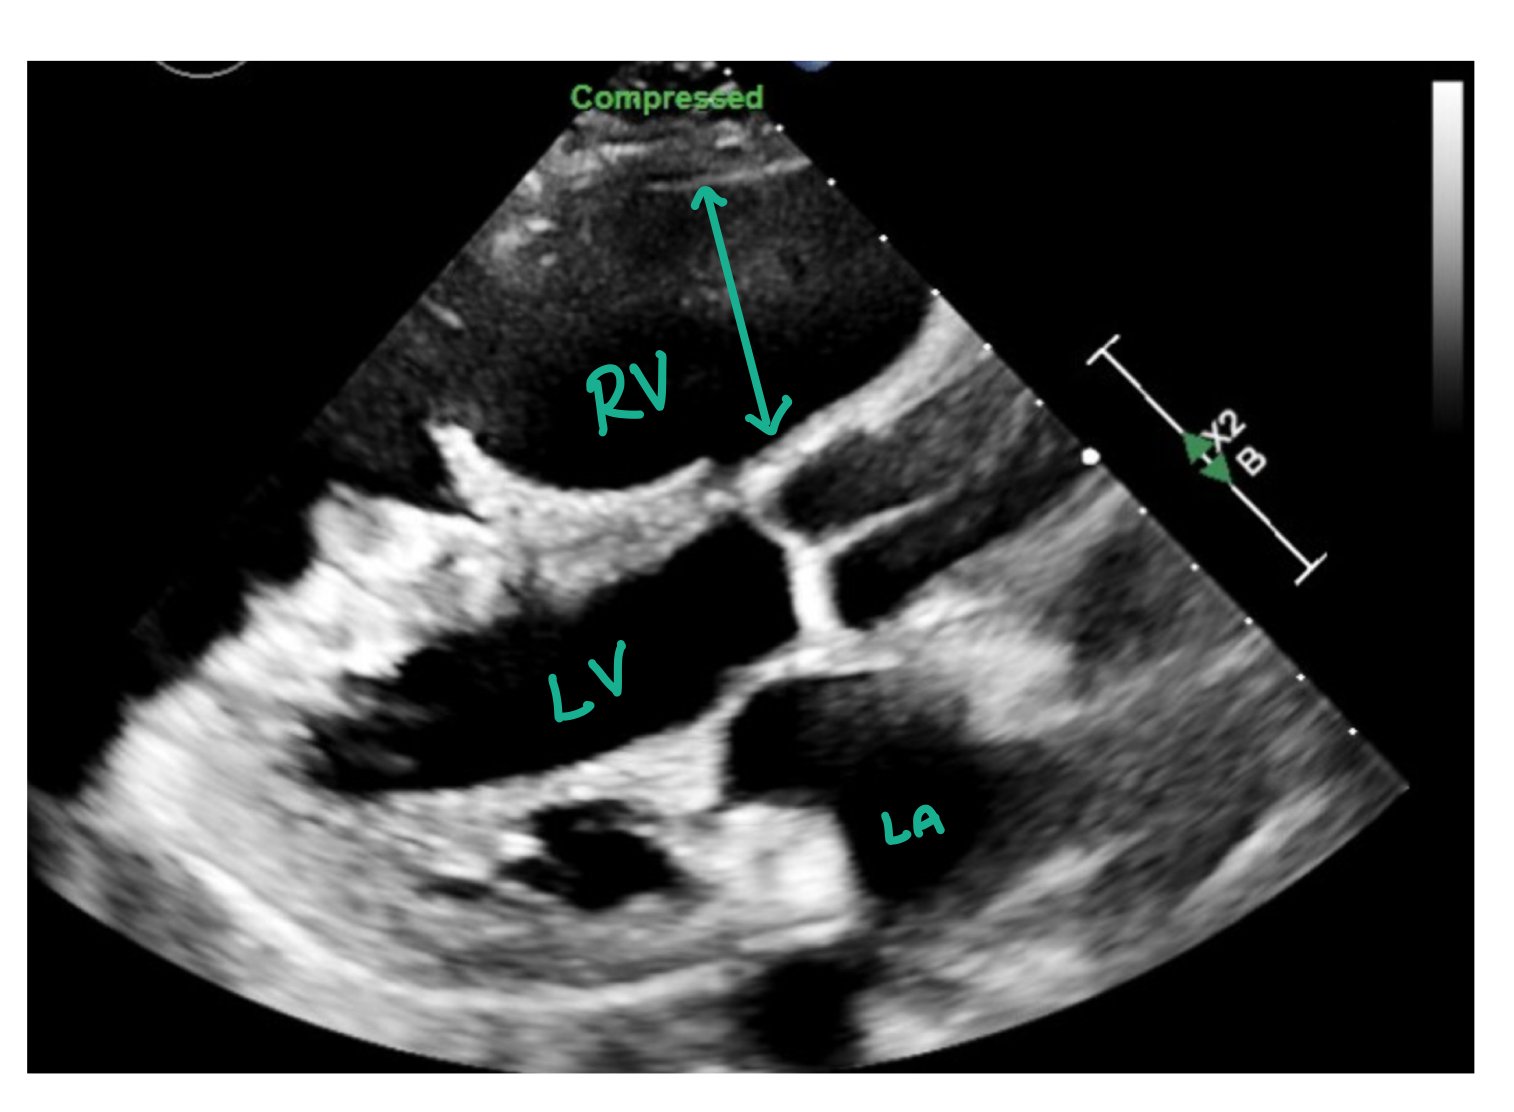

This image is a parasternal long axis depicting increased right ventricular (RV) pressure and size. Usually, the left ventricle (LV) should be greater than the RV. However, in this image, the RV is significantly enlarged which is consistent with increased right-sided pressures.

Here is a picture of the parasternal short axis. Again, note how the RV > LV, the D sign shape of the RV during systole with bowing of the intraventricular septum.